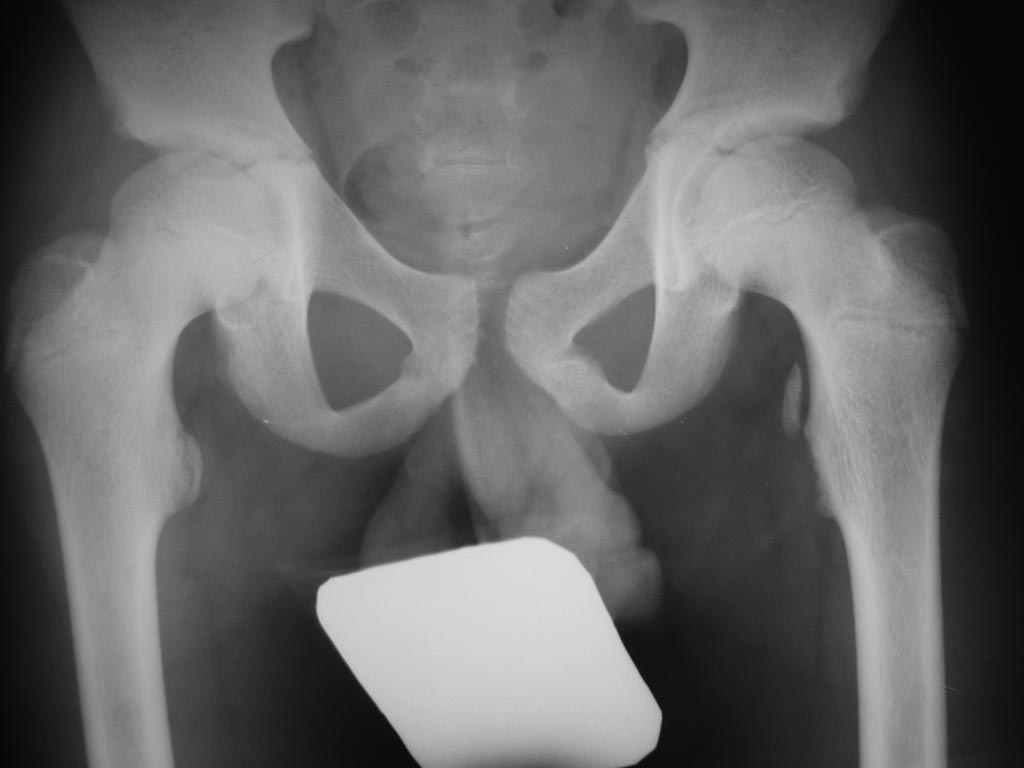

Пациент 12 лет Травма при неловкой постановке ноги во время бега

Диагноз: З/эпифизеолиз малого вертела левого бедра со смещением